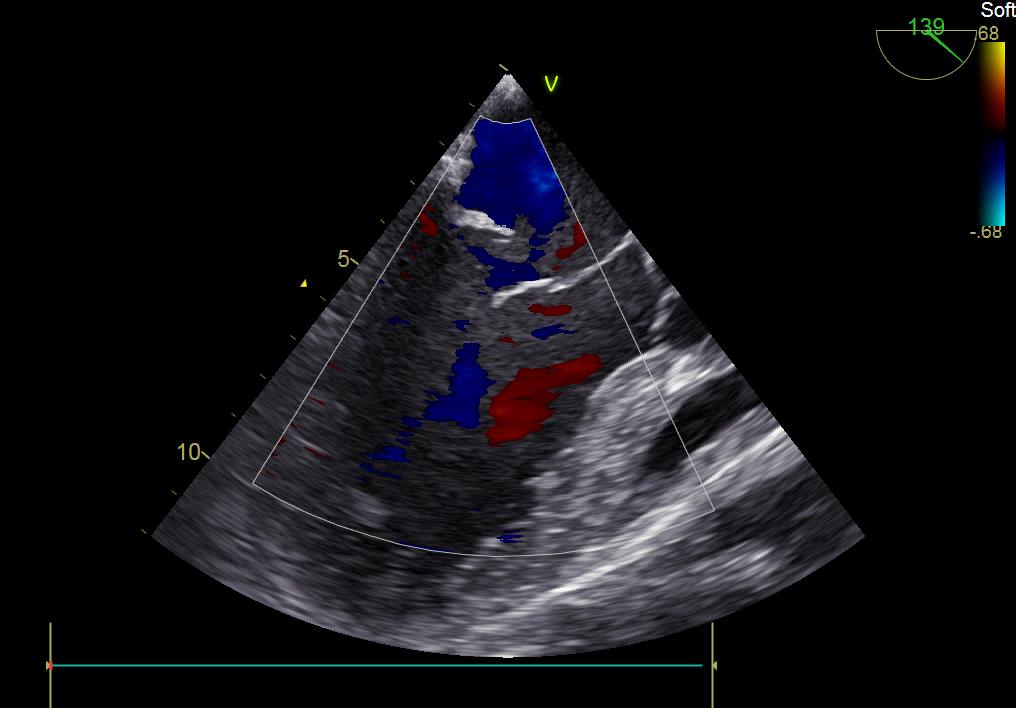

患者何某,42歲男性,因心功能不全入住我院心胸外科,心臟彩超提示二尖瓣后葉脫垂伴有重度返流及心臟擴大,在迅速糾正心衰后,手術便提上日程,心胸外科廖金文主任多次組織全科及兄弟科室討論,在二尖瓣置換及成形術上,最終決定采取二尖瓣成形術。為保證手術安全,討論圍手術期各個細節(jié),所謂細節(jié)決定成敗,因為術前的細致全面,加上術中的一絲不茍及術后的精細化管理,患者術后恢復順利,健康出院,復查心臟彩超未見二尖瓣返流。

術前彩超